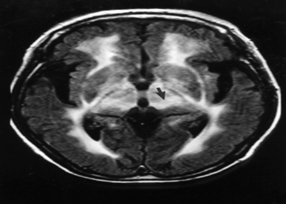

Haw River 증후군(Dentatorubro-Pallidoluysian atrophy(DRPLA))

증상

정신 지체

,

운동장애

뇌전증 발작

관련질환

헌팅톤 병

척수소뇌성 운동실조증

척수구근 근위축증

유약 X 증후군

프리이드라이히 운동실조증

근긴장성 이영양증

진료과

의학유전학센터

의학유전학과